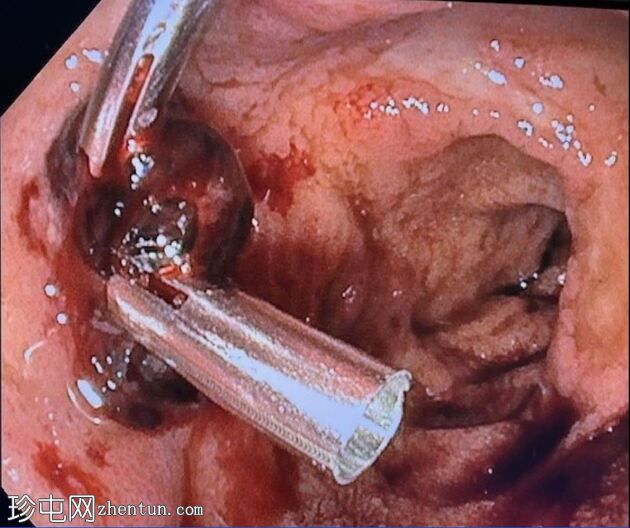

消化道内镜检查

8.jpeg

止血

及止血夹

内镜报告:

食管:LA C级食管炎。

胃:胃底可见变质血液及大血块。吸痰、冲洗并调整患者体位以移动血块后,未在胃底或胃体部发现病变。未发现活动性出血点。

胃窦:幽门前区可见三处溃疡,每处均小于1厘米,底部均清洁。

十二指肠:

D1:D1前壁可见一处含血块的溃疡。应用两个止血夹止血,并在溃疡周围注射1:10,000肾上腺素。

D2:D2可见两处溃疡。

CT血管造影对检测活动性消化道出血具有较高的敏感性。

患者立即接受了上消化道内镜检查。